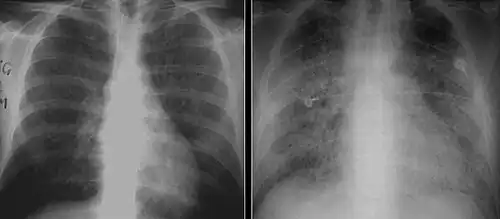

X-ray and CT of ground glass opacities and pneumothorax in pneumocystis pneumonia.[7]

Pneumothorax is a well-known complication of PCP.[8] Also, a condition similar to acute respiratory distress syndrome (ARDS) may occur in patients with severe Pneumocystis pneumonia, and such individuals may require intubation.[9]

The diagnosis can be confirmed by the characteristic appearance of the chest X-ray and an arterial oxygen level (PaO2) that is strikingly lower than would be expected from symptoms. Gallium 67 scans are also useful in the diagnosis. They are abnormal in about 90% of cases and are often positive before the chest X-ray becomes abnormal. Chest X-ray typically shows widespread pulmonary infiltrates. CT scan may show pulmonary cysts (not to be confused with the cyst-forms of the pathogen).